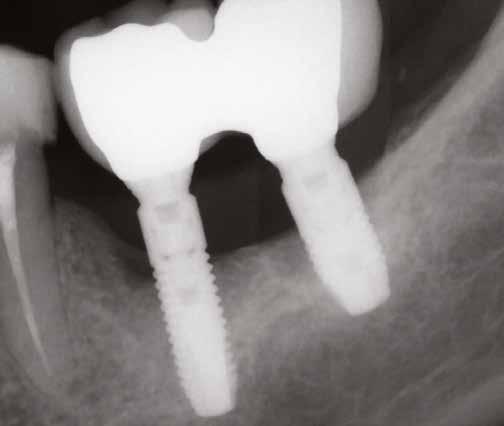

lási csavarokat (PEEK titáncsavarral) maximum 15 Ncm-rel húztuk meg (3–6. ábra). Az összes implantátum kiváló stabilitást mutatott (a mérésekhez Periotestet használtunk, a Medizintechnik Gulden jóvoltából), és teljesen osszeointegrálódott. Ezt a radiológiai vizsgálatok is megerősítették.

3. a–b ábra: Röntgenfelvételek három hónap után (a) és a gyógyulási csavarok behelyezve (b, 1. eset).

4. a–b ábra: Röntgenfelvételek öt hónappal később (a) és a gyógyulási csavarok behelyezve (b, 2. eset).

5. a–c ábra: Röntgenfelvételek öt hónappal később (a) és a gyógyulási csavarok behelyezve (b és c, 3. eset).

6. a–b ábra: Röntgenfelvételek öt hónappal később (a) és a gyógyulási csavarok behelyezve (b, 4. eset).